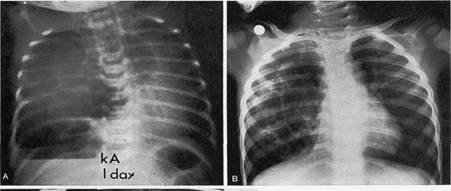

Мал.15. А. бронхогенна напружена кіста, зміщення межистіння.

Б. вигляд її на операції, кіста виходить з верхньої долі

Мал.16. Кістадематозна аномалія у новонародженої дитини.

А. З клінічними ознаками респіраторного дистреса.

Б. Без них.